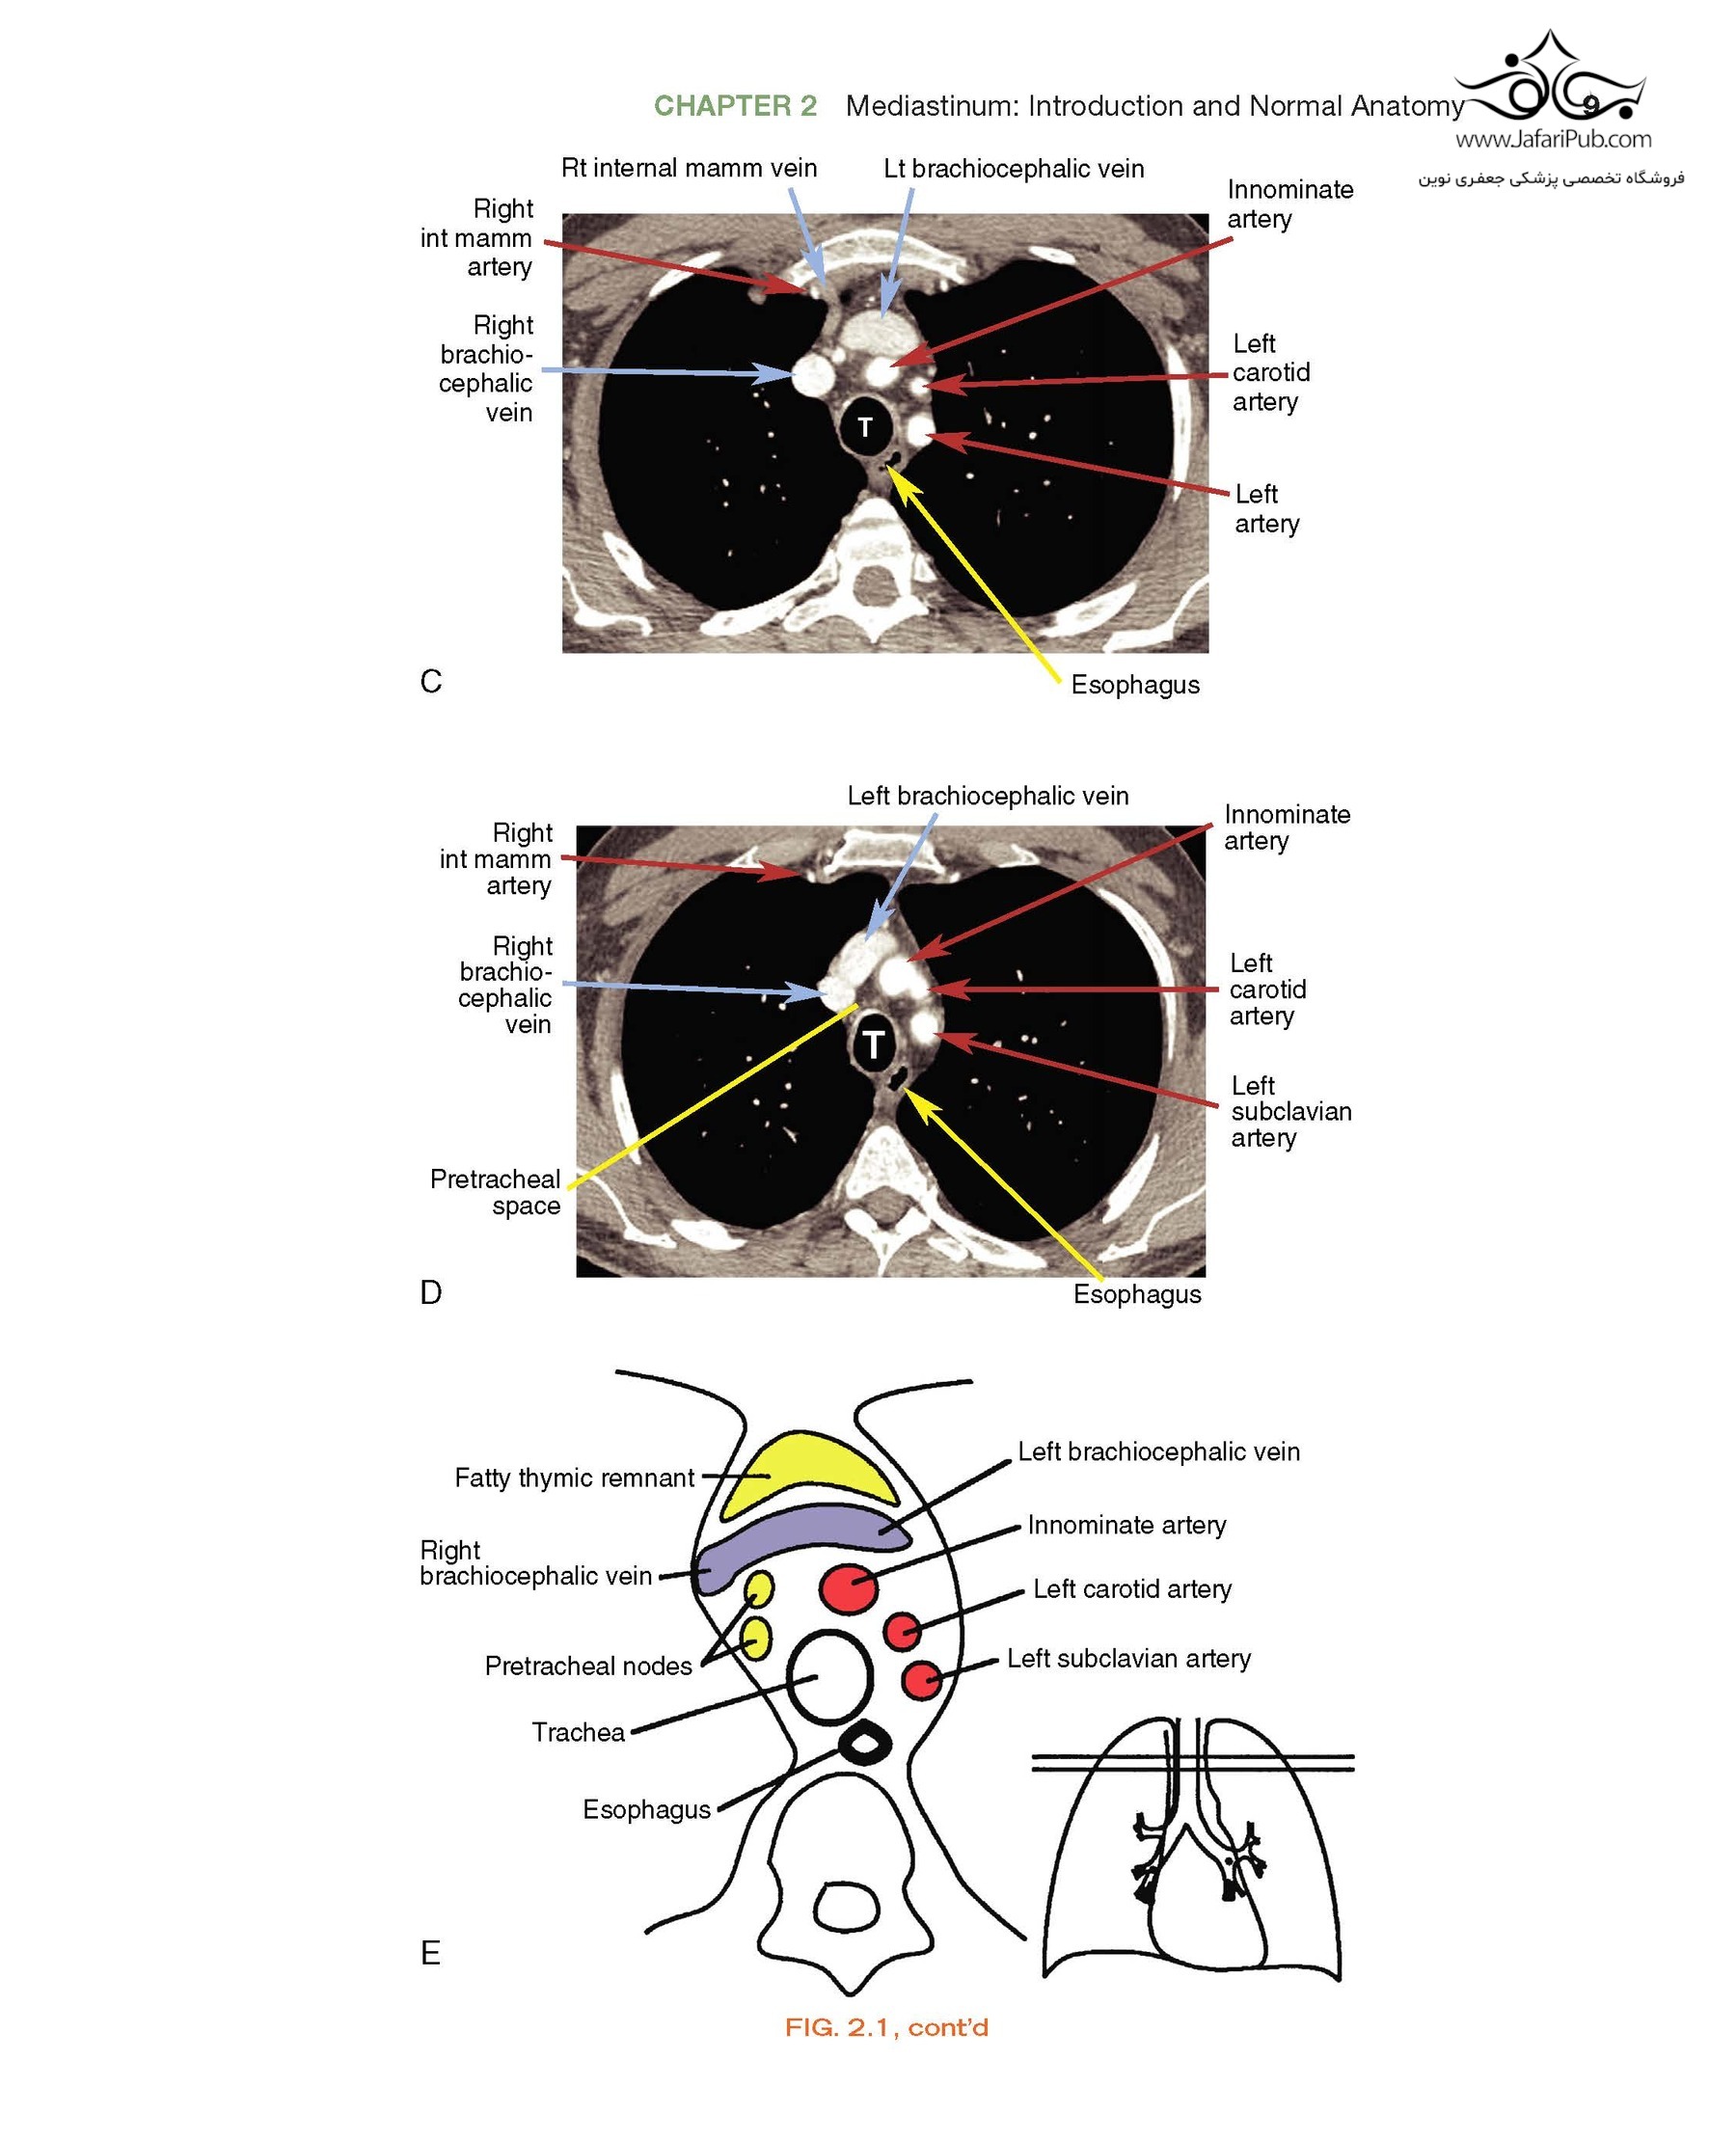

Features many new topics, discussions of additional diseases, and new, high-quality images from cover to cover, including updated descriptions and illustrations of normal anatomy and incidental findings.